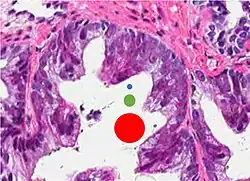

- Relatively common and highly specific

- [4]

- Multiple nucleoli

- Eccentric nucleoli[4]

-

Acinar adenocarcinoma with multiple nucleoli. -

Acinar adenocarcinoma with double and eccentric nucleoli.